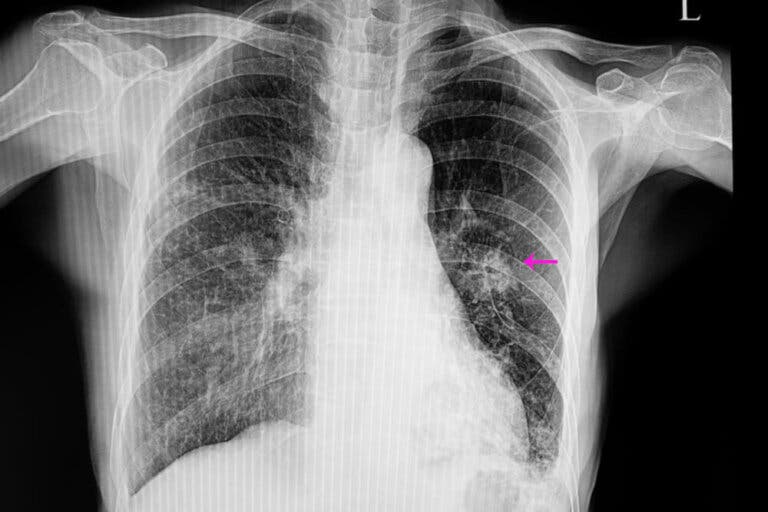

El nódulo pulmonar puede detectarse accidentalmente en una radiografía

En estos casos, los nódulos suelen tener un aspecto irregular en la radiografía, con unos bordes mal definidos; de ahí el término «neoplásico». También suelen ser de menor tamaño que los benignos y, además, se asocian a ciertos factores de riesgo, como los siguientes:

Una vez hecho esto, es necesario realizar ciertas pruebas de imagen para localizar el nódulo. Además, las imágenes permiten observar ciertas características como la forma y el tamaño, que son importantes para diferenciar uno benigno de uno posiblemente maligno.

Las más utilizadas son la radiografía de tórax y la tomografía computarizada. Para conocer exactamente la causa del nódulo pulmonar, en ocasiones se realizan biopsias que permiten analizar el tejido que lo forma.